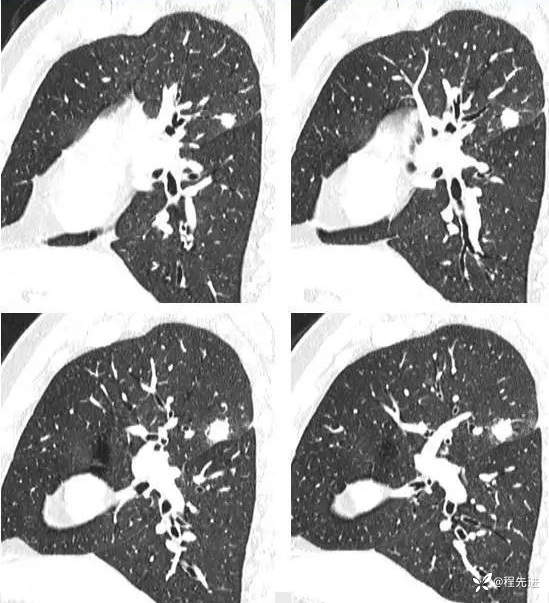

肺窗